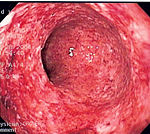

At the time of colonoscopy, biopsies of the colon are often taken in order to confirm the diagnosis. There are certain characteristic features of the pathology seen that point toward Crohn's disease. Crohn's disease shows a transmural pattern of inflammation, meaning that the inflammation may span the entire depth of the intestinal wall. Grossly, ulceration is an outcome seen in highly active disease. There is usually an abrupt transition between unaffected tissue and the ulcer. Under a microscope, biopsies of the affected colon may show mucosal inflammation. This inflammation is characterized by focal infiltration of neutrophils, a type of inflammatory cell, into the epithelium. This typically occurs in the area overlying lymphoid aggregates. These neutrophils, along with mononuclear cells, may infiltrate into the crypts leading to inflammation (crypititis) or abscess (crypt abscess). Granulomas, aggregates of macrophage derivatives known as giant cells, are found in 50% of cases and are most specific for Crohn's disease. The granulomas of Crohn's disease do not show "caseation", a cheese-like appearance on microscopic examination that is characteristic of granulomas associated with infections such as tuberculosis. Biopsies may also show chronic mucosal damage as evidenced by blunting of the intestinal villi, atypical branching of the crypts, and change in the tissue type ( metaplasia). One example of such metaplasia, Paneth cell metaplasia, involves development of Paneth cells (typically found in the small intestine) in other parts of the gastrointestinal system.